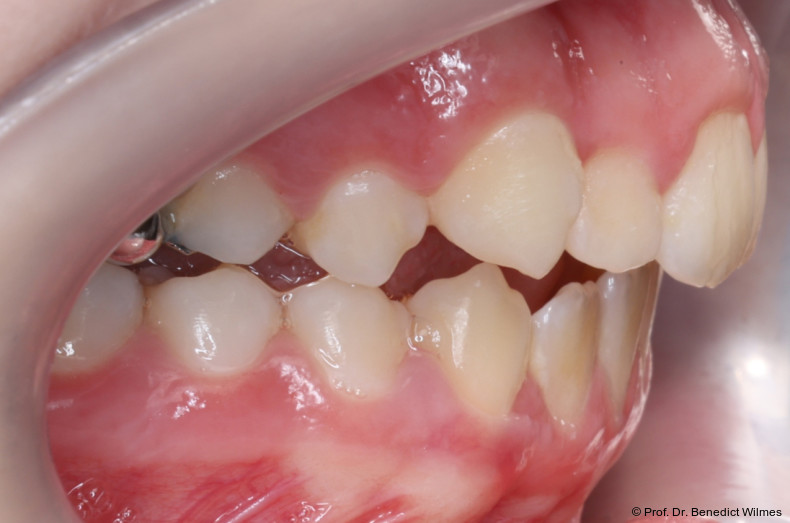

Eine 13-jährige Patientin stellte sich mit beidseitigem Kreuzbiss, einem anterioren offenen Biss und einer Angle Klasse II vor. Das viszerale Schluckmuster wurde mittels logopädischer Maßnahmen umgestellt, der offene Biss persistierte jedoch (Abb. 3a–l).

Als alternative Therapie wurde die chirurgische Korrektur des offenen Bisses nach Abschluss des Wachstums vorgeschlagen. Eltern und Patientin entschieden sich allerdings für die non­chirurgische und weniger invasive Molarenintrusion.